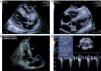

Ficou internado com o diagnóstico de pneumonia adquirida na comunidade. Contudo, verificou-se ausência de resposta terapêutica face a múltiplos e sequenciais esquemas de antibióticos, apresentando deterioração progressiva do estado geral. Face a esta evolução desfavorável, realizou um ecocardiograma transtorácico (ecógrafo Acuson SC 2000 Siemens; sonda 8v3c), que revelou uma volumosa massa infiltrativa (45 x 40mm), ao nível do ápex do ventrículo direito (VD), estendendo-se ao longo do septo interventricular e revestindo toda a parede livre do VD até à câmara de saída (Figura 2). A massa era ecodensa, apresentava bordos definidos, textura heterogénea e ausência de sinais de vascularização com o fluxo Doppler cor. Apesar de se verificar uma discreta aceleração do fluxo ao nível da câmara de saída do VD, não condicionava obstrução significativa a este nível (Figura 2D). Mantinha boa função sistólica biventricular.

(A-D) Ecocardiograma transtorácico, mostrando a presença de massa infiltrativa ao nível do VD (seta), envolvendo toda a região apical, septo interventricular e parede livre do VD, não condicionando obstrução significativa ao nível da câmara de saída do VD (2D). AD: aurícula direita; AE: aurícula esquerda; SIV: septo interventricular; VD: ventrículo direito; VE: ventrículo esquerdo.